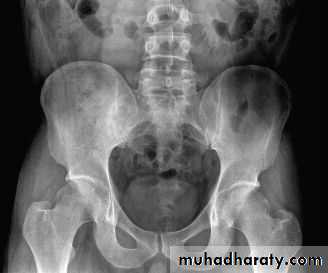

ANKYLOSING SPONDYLITIS (AS)

• Seronegative spondyloarthropathy of the axial skeleton and proximal large joints.• Clinical: males >> females. HLA-B27 in 95%. Insiduous onset of back pain and stiffness. Onset: 20 years.

• Radiographic features

• * SI joint is the initial site of involvement:

• bilateral, symmetrical

• Erosions: early ,Sclerosis: intermediate , ankylosis: late

• * Contiguous thoracolumbar involvement

• Vertebral body "squaring": early osteitis

• * Syndesmophytes

• * Bamboo spine: late fusion and Bamboo spine

• ligamentous ossification

• *ankylosed spine (fracture)

• * Enthesopathy is common(("whiskering of tuberosities )

• * Arthritis of proximal joints (hip > shoulder) in 50% ,erosions and osteophytes